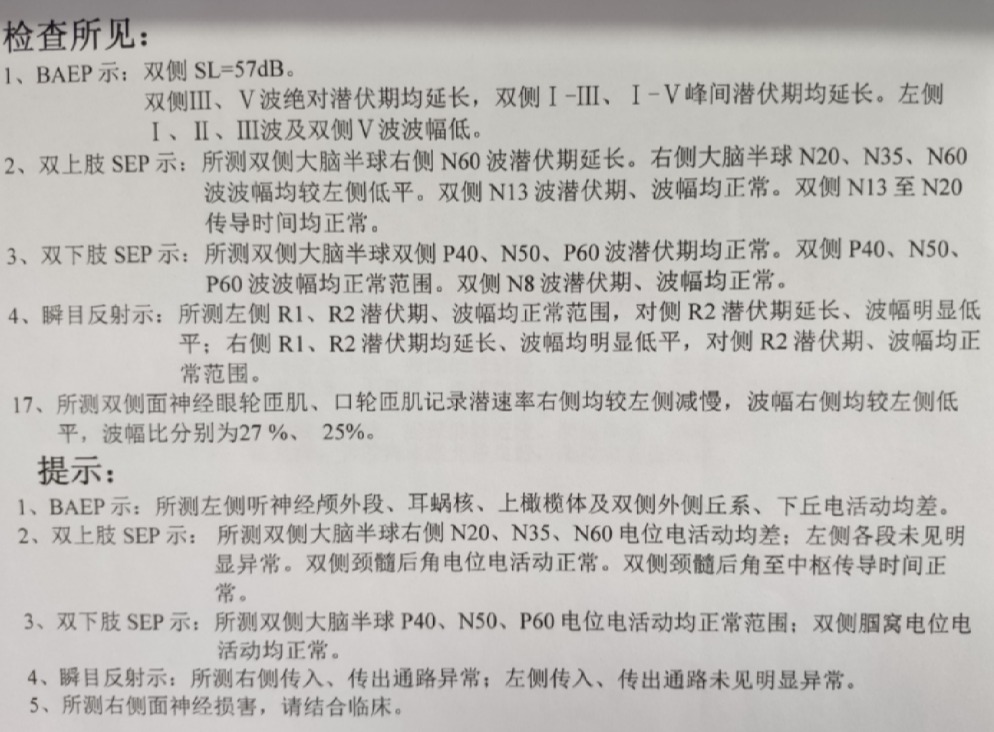

术前神经电生理检查如下:说明患者已经造成了实质性神经功能损害。术中神经电声监测未见损害增加。